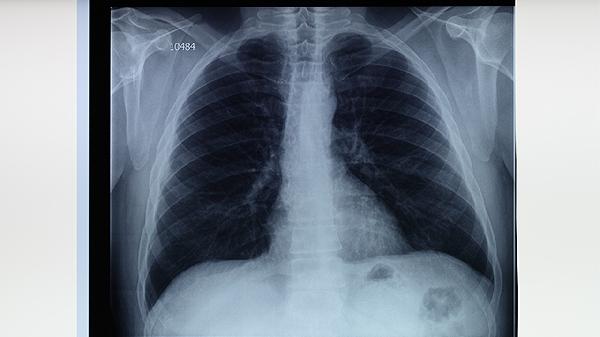

肺结核治愈一年通常可以跑步,但需根据个体恢复情况逐步增加运动强度。肺结核是由结核分枝杆菌感染引起的慢性传染病,经过规范抗结核治疗后,多数患者肺功能可逐渐恢复。

治愈一年后若复查显示肺部病灶完全吸收、无活动性病变且肺功能正常,可尝试低强度有氧运动如慢跑。初期建议选择平坦场地,控制心率在每分钟100-120次,单次持续时间不超过30分钟,每周3-4次为宜。运动时注意监测呼吸状态,出现胸闷气促应立即停止。恢复期跑步有助于改善心肺功能,但需避免剧烈运动导致过度换气。

若存在肺纤维化等后遗症或合并其他基础疾病,需经呼吸科医生评估后制定运动方案。部分患者可能因胸膜粘连出现运动后胸痛,或因残留病灶影响气体交换效率。这类情况建议优先选择游泳、太极拳等低冲击运动,跑步时应配备血氧监测设备,避免在高污染环境或寒冷天气户外运动。